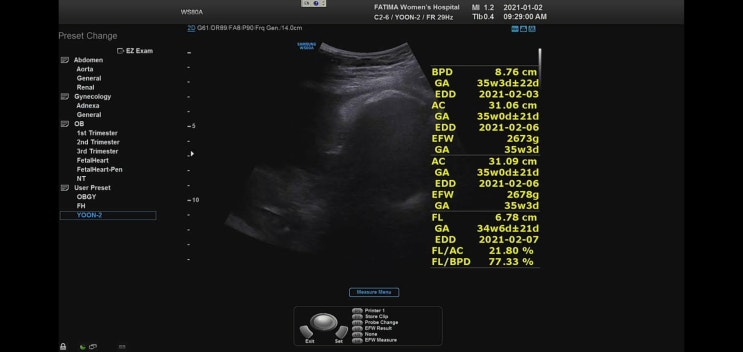

임신36주차 (정기검진, 막달검사)

#36주증상 ▶ 잠이 많아짐 ▶ 오른쪽 가슴아래 갈비뼈 부분 통증 ▶ 현기증 ▶ 태동 활발 #36주해야할일 ▶...